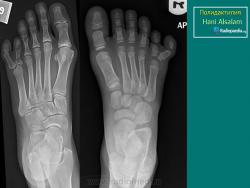

КСС. Аномалии и варианты развития. Нижняя конечность. +

Аномалии и варианты развития.  Нижняя конечность.